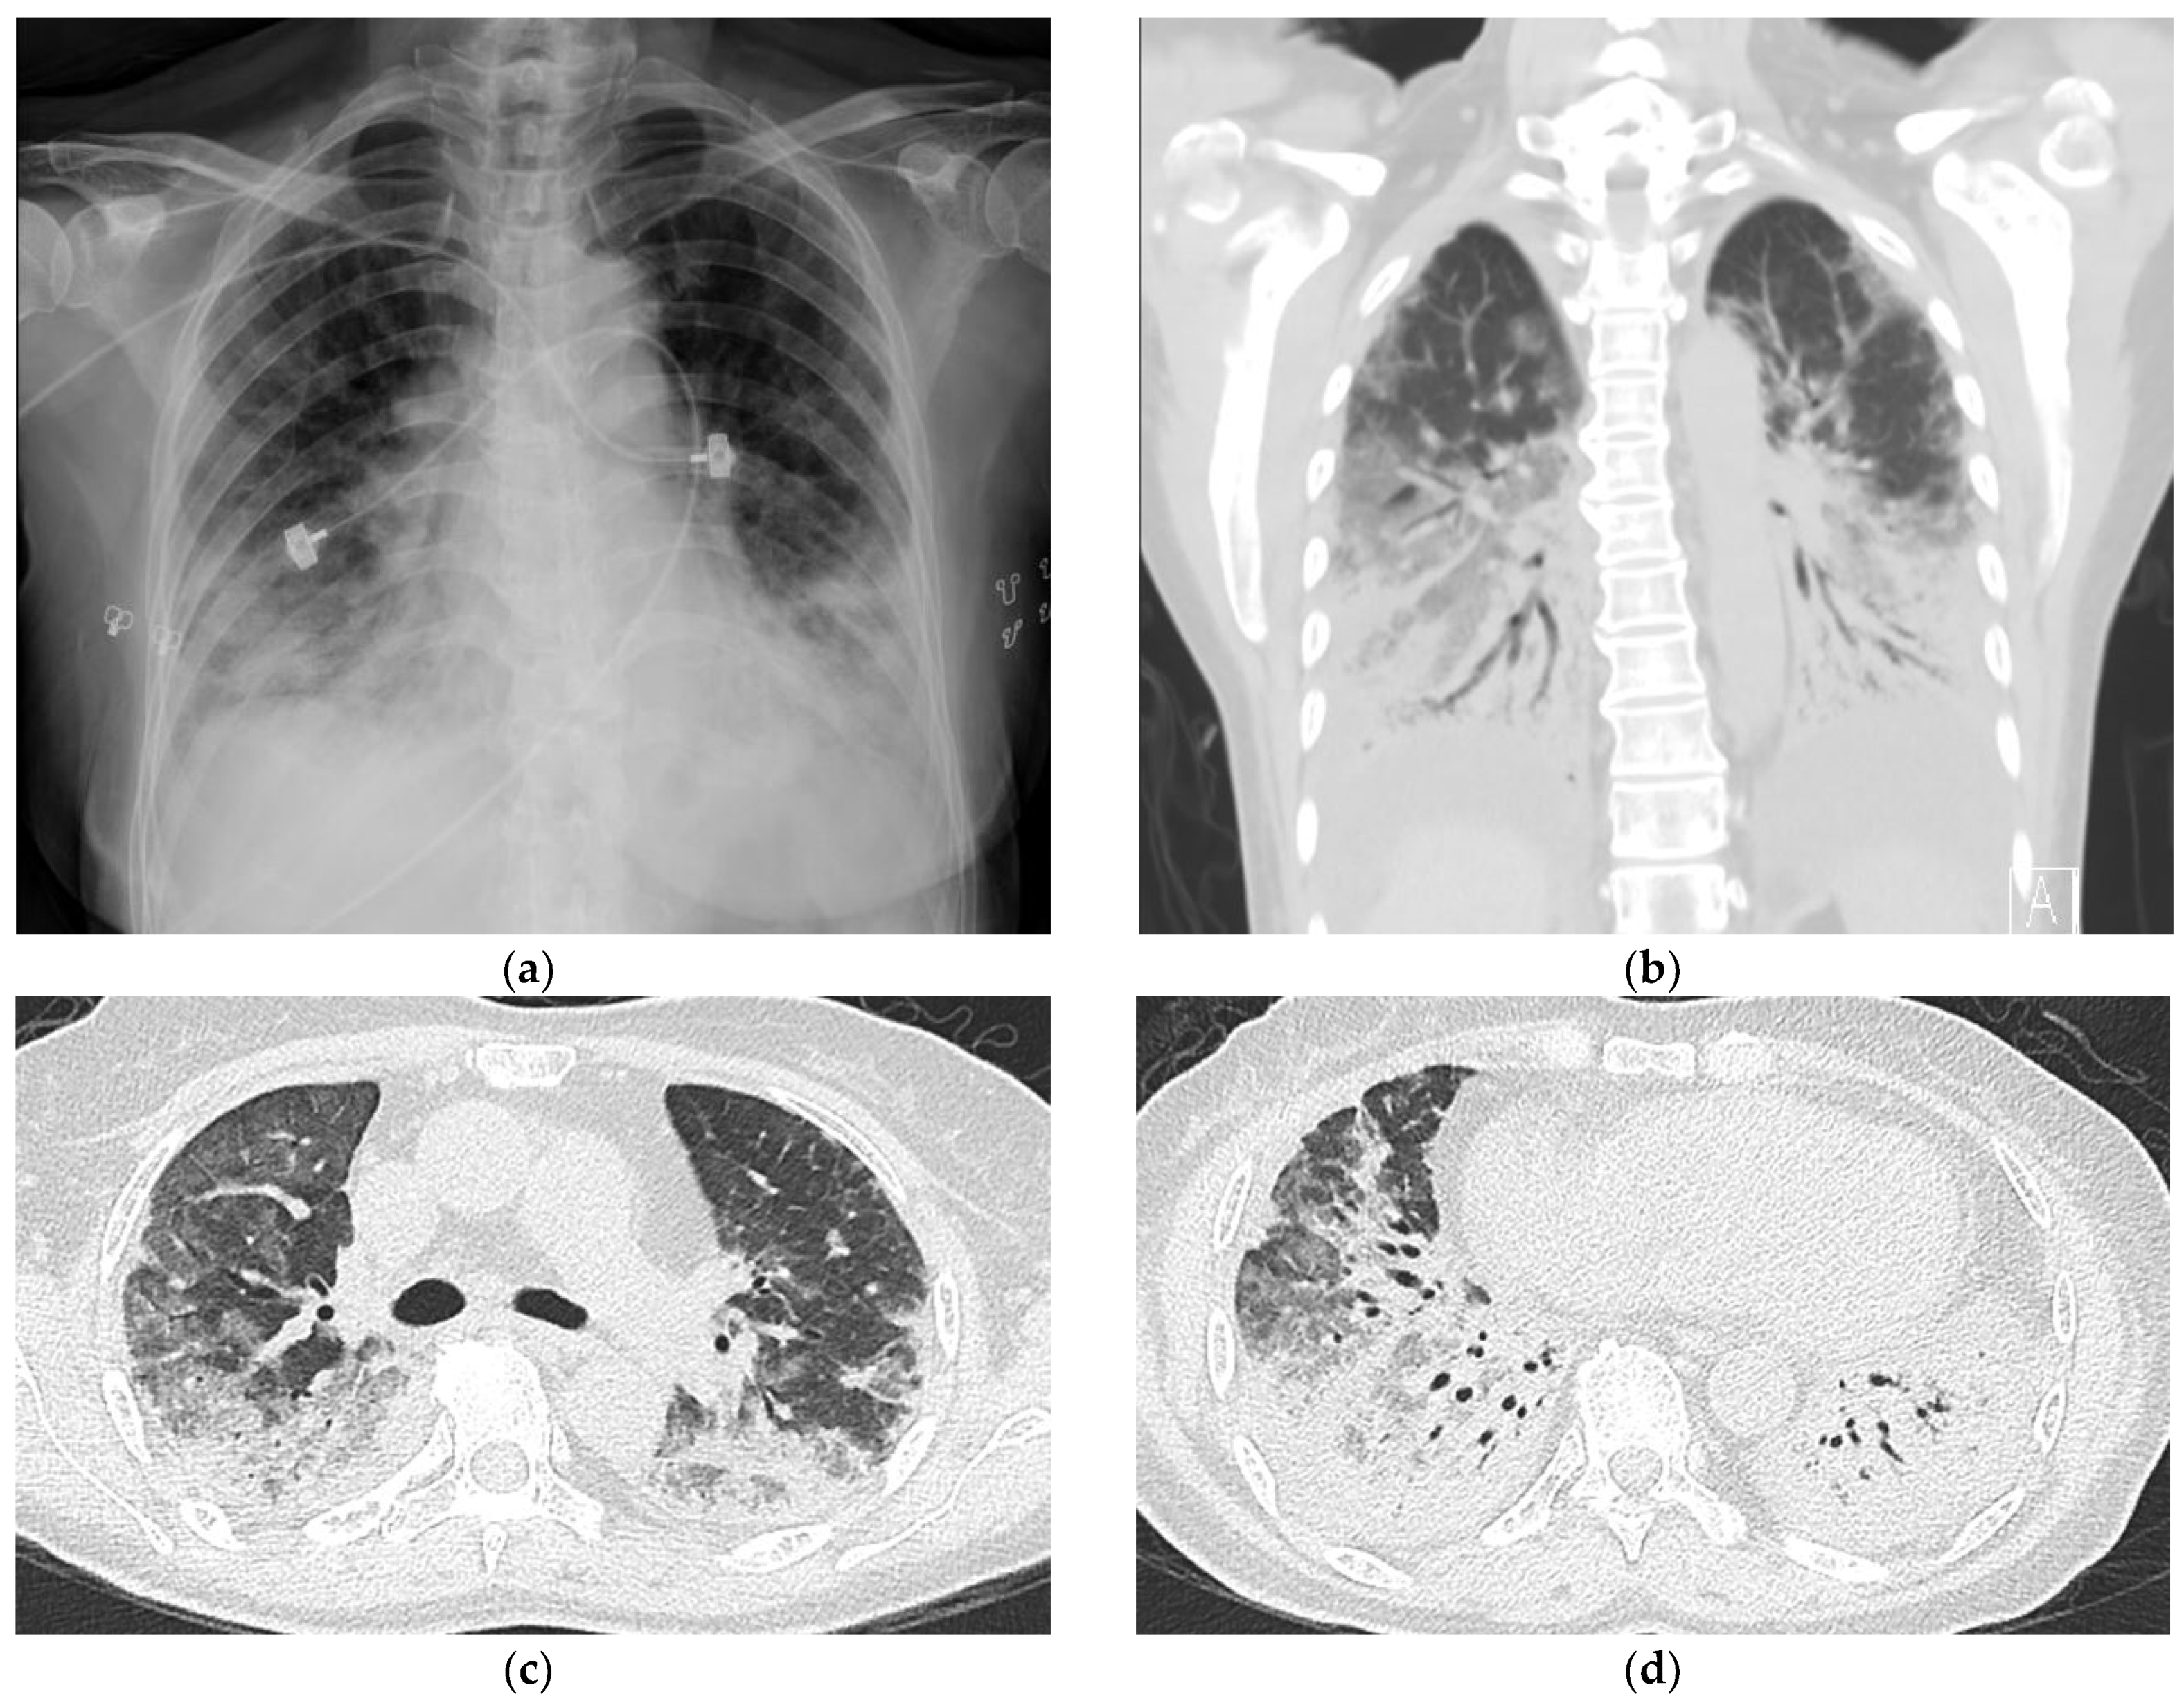

2. Case Report